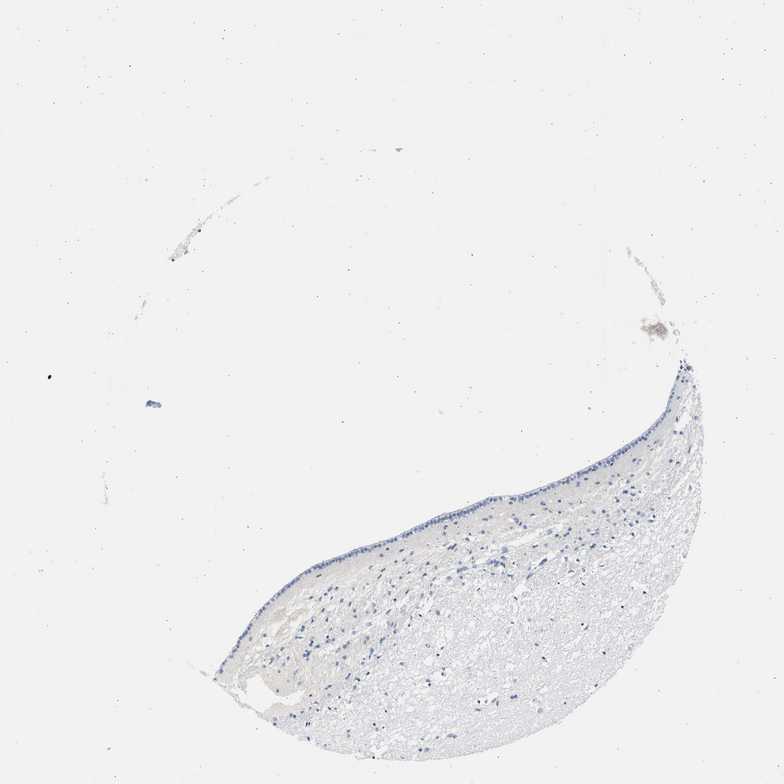

CAUDATE - Antibody stainingi

Antibody staining in the annotated cell types in the current human tissue is reported as not detected, low, medium, or high, based on conventional immunohistochemistry profiling in selected tissues. This score is based on the combination of the staining intensity and fraction of stained cells.

Each image is clickable and will lead to virtual microscopy that enables deeper exploration of all samples and also displays staining intensity scores, fraction scores and subcellular localization as well as patient and tissue information for each sample.

Antibody HPA026813Antibody CAB020824

Glial cells Not detectedNot detected

Neuronal cells LowNot detected